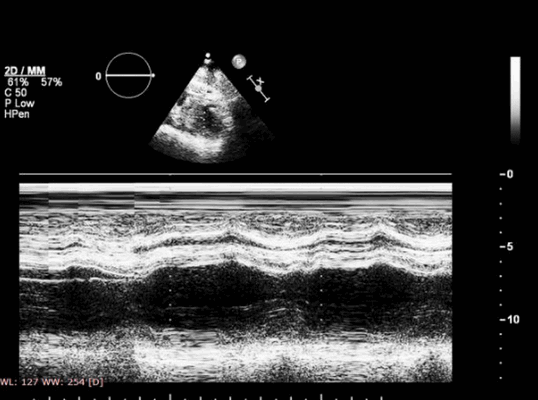

Наши аппараты для УЗИ сердца позволяют выполнять различные варианты эхокардиографии. Одномерная ЭхоКГ в М-режиме, позволяет в виде графика воспроизвести движение сердечных стенок и клапанов, что дает оценить функцию желудочков.

Указанные изменения можно обнаружить с помощью двумерной эхокардиографии, но M-режим также чрезвычайно хорош, поскольку его высокая частота дискретизации делает его очень чувствительным к движению стенок и аномалиям утолщения. Важно, чтобы курсор располагался под углом 90° к стенке. Есть ограниченные области миокарда ЛЖ, которые можно исследовать в М-режиме - наиболее полезно задняя стенка и МЖП. Изменения обратимы, если ишемия кратковременная, например в покое, прием антиангинальных препаратов, проведенная вовремя чрескожная транслюминальная коронарная ангиопластика, тромболизис или аортокоронарное шунтирование (АКШ). Если кровоснабжение миокарда прервано более чем на 1 час, происходят необратимые изменения, включающие инфаркт миокарда и рубцевание.

В сочетании М-режима и тканевой цветовой доплерографии измеряется максимальный систолический диаметр восходящего отдела грудной аорты (Дс) и минимальный диастолический диаметр восходящего отдела грудной аорты (Дд) за 3 последовательных сердечных цикла при скорости развертки 50-100 мм/с при параллельной записи ЭКГ с курсором, перпендикулярным к стенке сосуда. За диаметр принимается расстояние между внутренними поверхностями ближней и дальней стенок восходящего отела грудной аорты. Максимальный систолический диаметр измеряется на границе перехода красного цвета тканевой цветовой доплерографии в синий, что отображает окончание движения и максимальное смещение восходящего отдела грудной аорты. Минимальный диастолический диаметр измеряется на границе перехода синего цвета тканевой цветовой доплерографии в красный, что отображает окончание движения и максимальное смещение восходящего отдела грудной аорты. Измерение диаметра восходящего отдела грудной аорты проводится на участке на 3 см выше фиброзного кольца аортального клапана. Далее, используя полученные значения систолического и диастолического диаметра восходящего отдела грудной аорты, артериального давления, вычисляются стандартные показатели упруго-эластических свойств аорты, предложенные на Первой международной конференции согласия, прошедшей в Париже в 2000 г. под председательством M. Safar и E. Frohlich [O’Rourke, 2002]: коэффициент растяжимости (СD = 2∆Д/Дд х ПАД), коэффициент податливости (СС = π х (Дс 2 - Дд 2 )/4 х ПАД), модуль эластичности (жесткости) Петерсона (Ep = ПАД х Дд /∆Д), индекс жесткости (SI = ln(САД/ДАД) / [(Дс - Дд) /Дд]) (рис. 1).

Рис. 1. М-режим ТДИ восходящего отдела аорты. Левая парастернальная позиция по длинной оси на уровне 3 см выше аортального клапана. Метки движения стенок устанавливаются в пограничных точках окрашивания движения стенок к датчику (1) в фазу изометрического расслабления ЛЖ, и от датчика (2) в фазу изометрического сокращения ЛЖ. Диаметр аорты измеряется по внутренним краям стенки